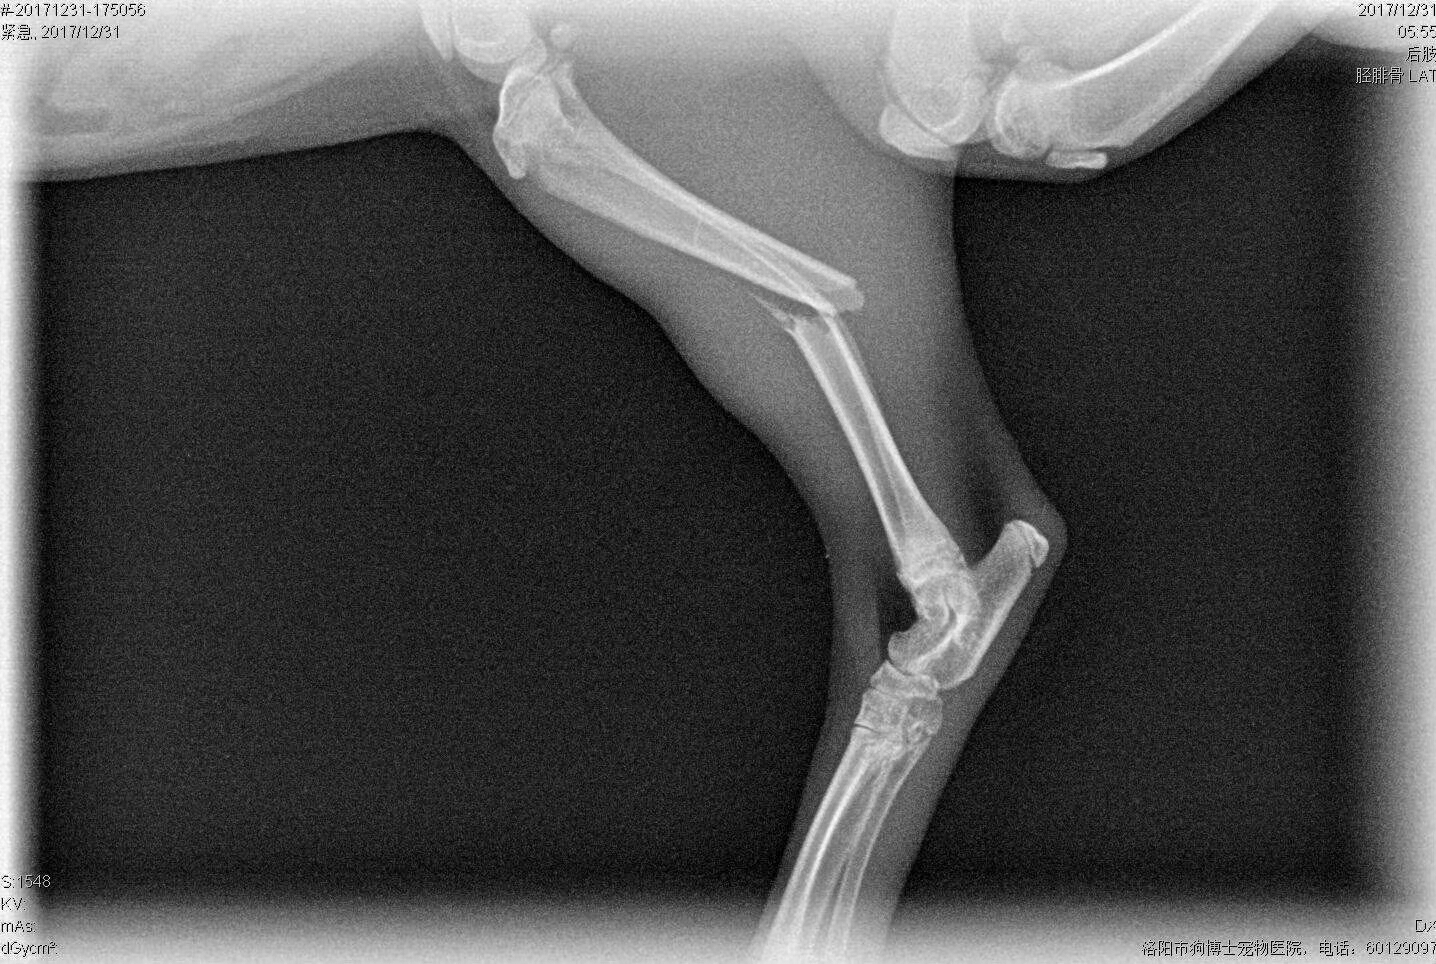

英短貓咪后肢脛骨腓骨骨折內(nèi)固定手術(shù)一例,住院護理中。